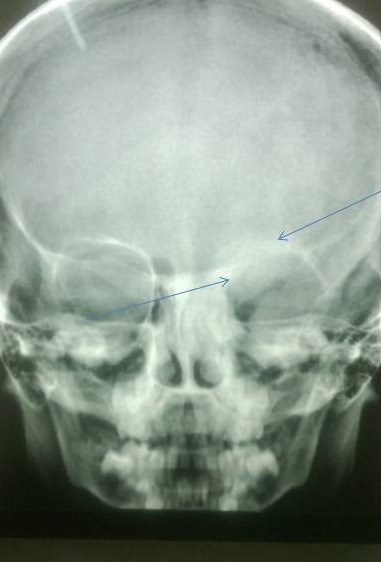

X-ray of the lower limbs showed fibrous dysplasia involving the left femur [Figure 2] and skull x-ray showed ground glass appearance of the left orbit. [Figure 3]

Figure 3. Lesions showing ground glass haze are seen involving roof, lateral and medial walls of left orbit